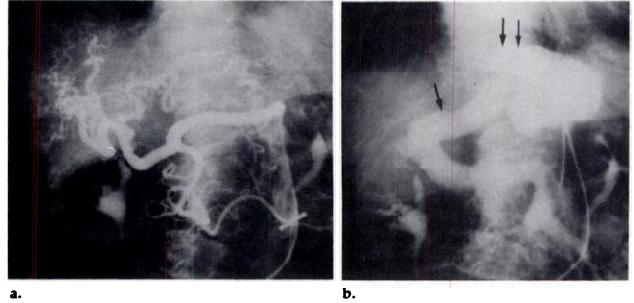

Figure 2. Case 1. Celio-mesentenic angiognaphy shows dilatation of the hepatic antery

and its tortuous branches (a); in the venous phase (b), the dilated left portal vein

(single arrow) feeds the fistula, which also communicates with the dilated left hepatic

vein (double arrows).

Figures 5-7. Case 2. (5) Transverse sonogram demonstrates a complex of branched venous channels within the posterior segmentof the night lobe of the liven; this malformation communicates with the night portal vein (single arrow) and with a right accessoryhepatic vein (double arrows). (6) Hepatic venognam obtained after injection of contrast medium in the accessory hepatic vein(single arrow) shows opacification of the venous malformation, right hepatic vein (double arrows) and the vena cava. (7) Venous phase of the mesentenic angiography demonstrates the right portal vein (arrow) feeding the fistula that flows into the accessory(double arrows) and right hepatic (triple arrows) veins.

Sonograms (Fig. 5) demonstrated a complex of branched venous channels within the posterior segment of the night lobe of the liver; this malformation communicated with the right portal vein and with a night accessory hepatic vein that joined the inferior vena cava under the confluence of the three hepatic veins. The hepatic venognam (Fig. 6) revealed normal free pressure measurements. Injection of contrast

medium in the accessory hepatic vein opacified the venous malformation, the night hepatic vein, and the inferior vena cava. The venous phase of mesentenic angiognaphy (Fig. 7) demonstnated the night portal vein feeding the malformation, which flowed into the accessory and the night hepatic veins. Simple dietetic treatment nelieved the hypoglycemic symptoms of this patient.